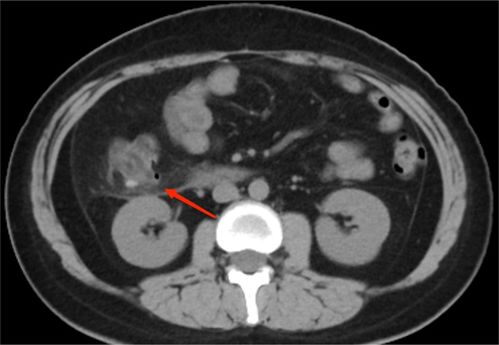

1. 消化系统疾病:胃炎、胃溃疡、肠易激综合征、阑尾炎、胆囊炎、胰腺炎……这些疾病都可能让你肚子疼得死去活来。

3. 泌尿系统疾病:尿路感染、肾结石、膀胱炎……这些疾病也可能让你肚子疼得坐立不安。